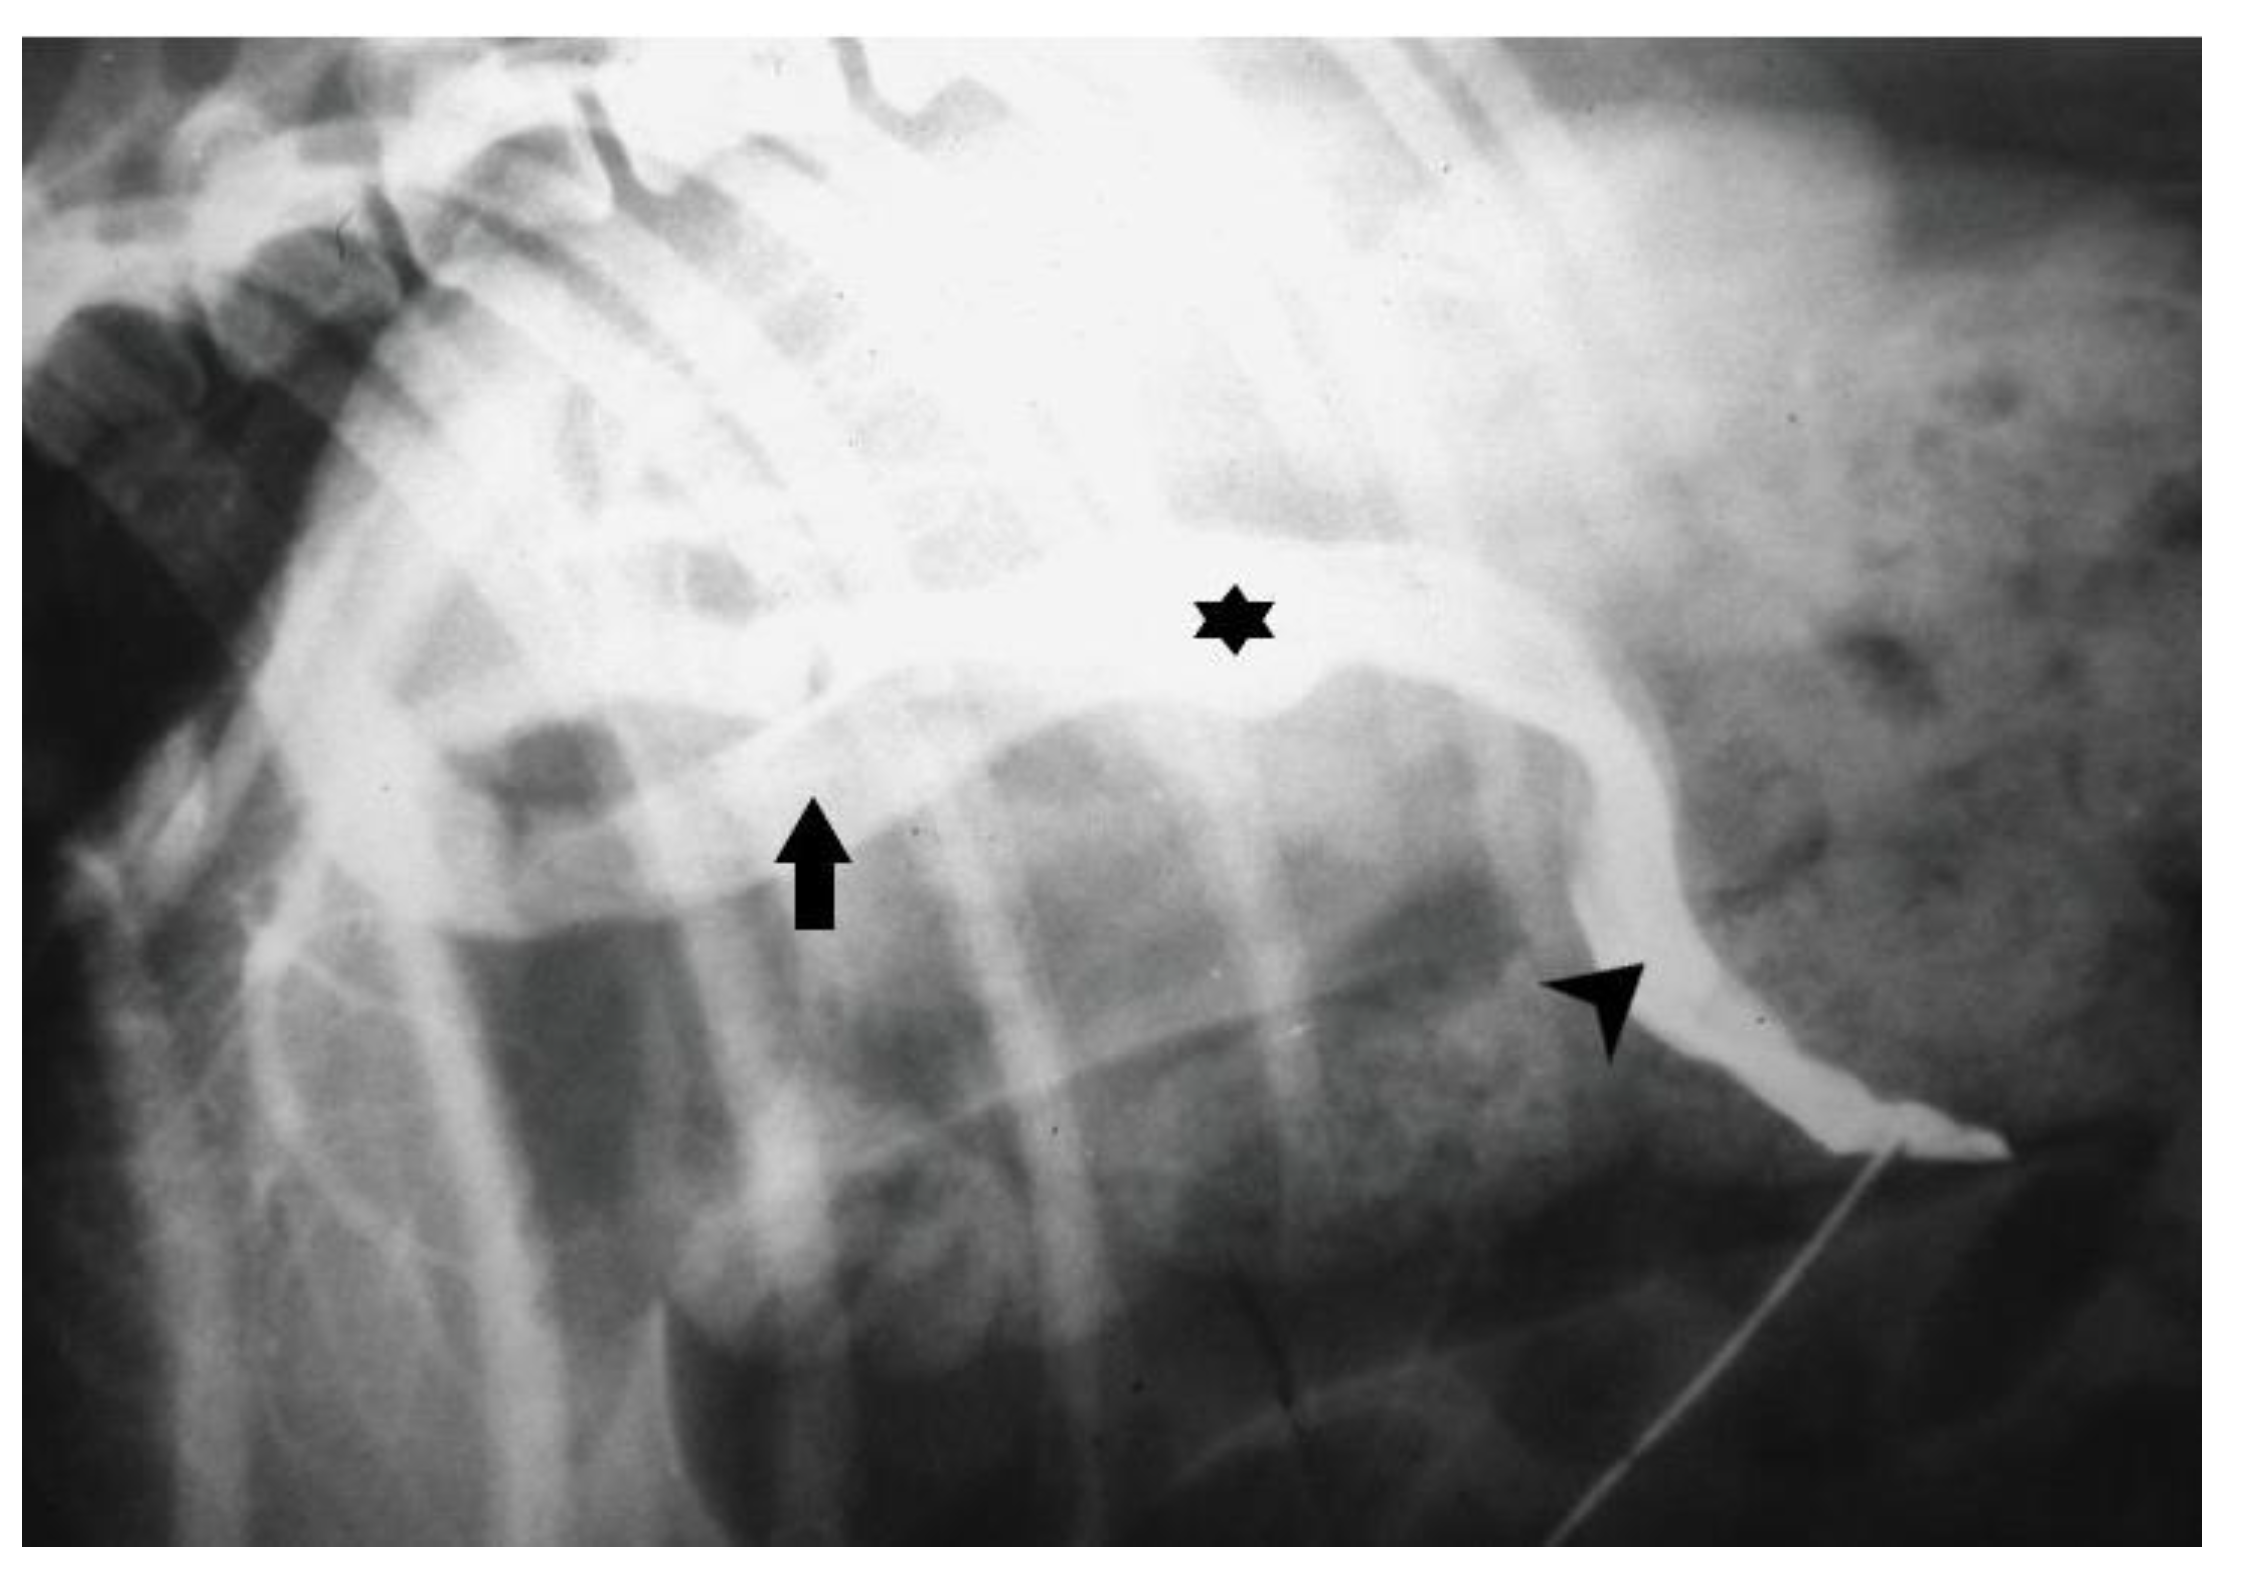

9. Diagnostic Imaging